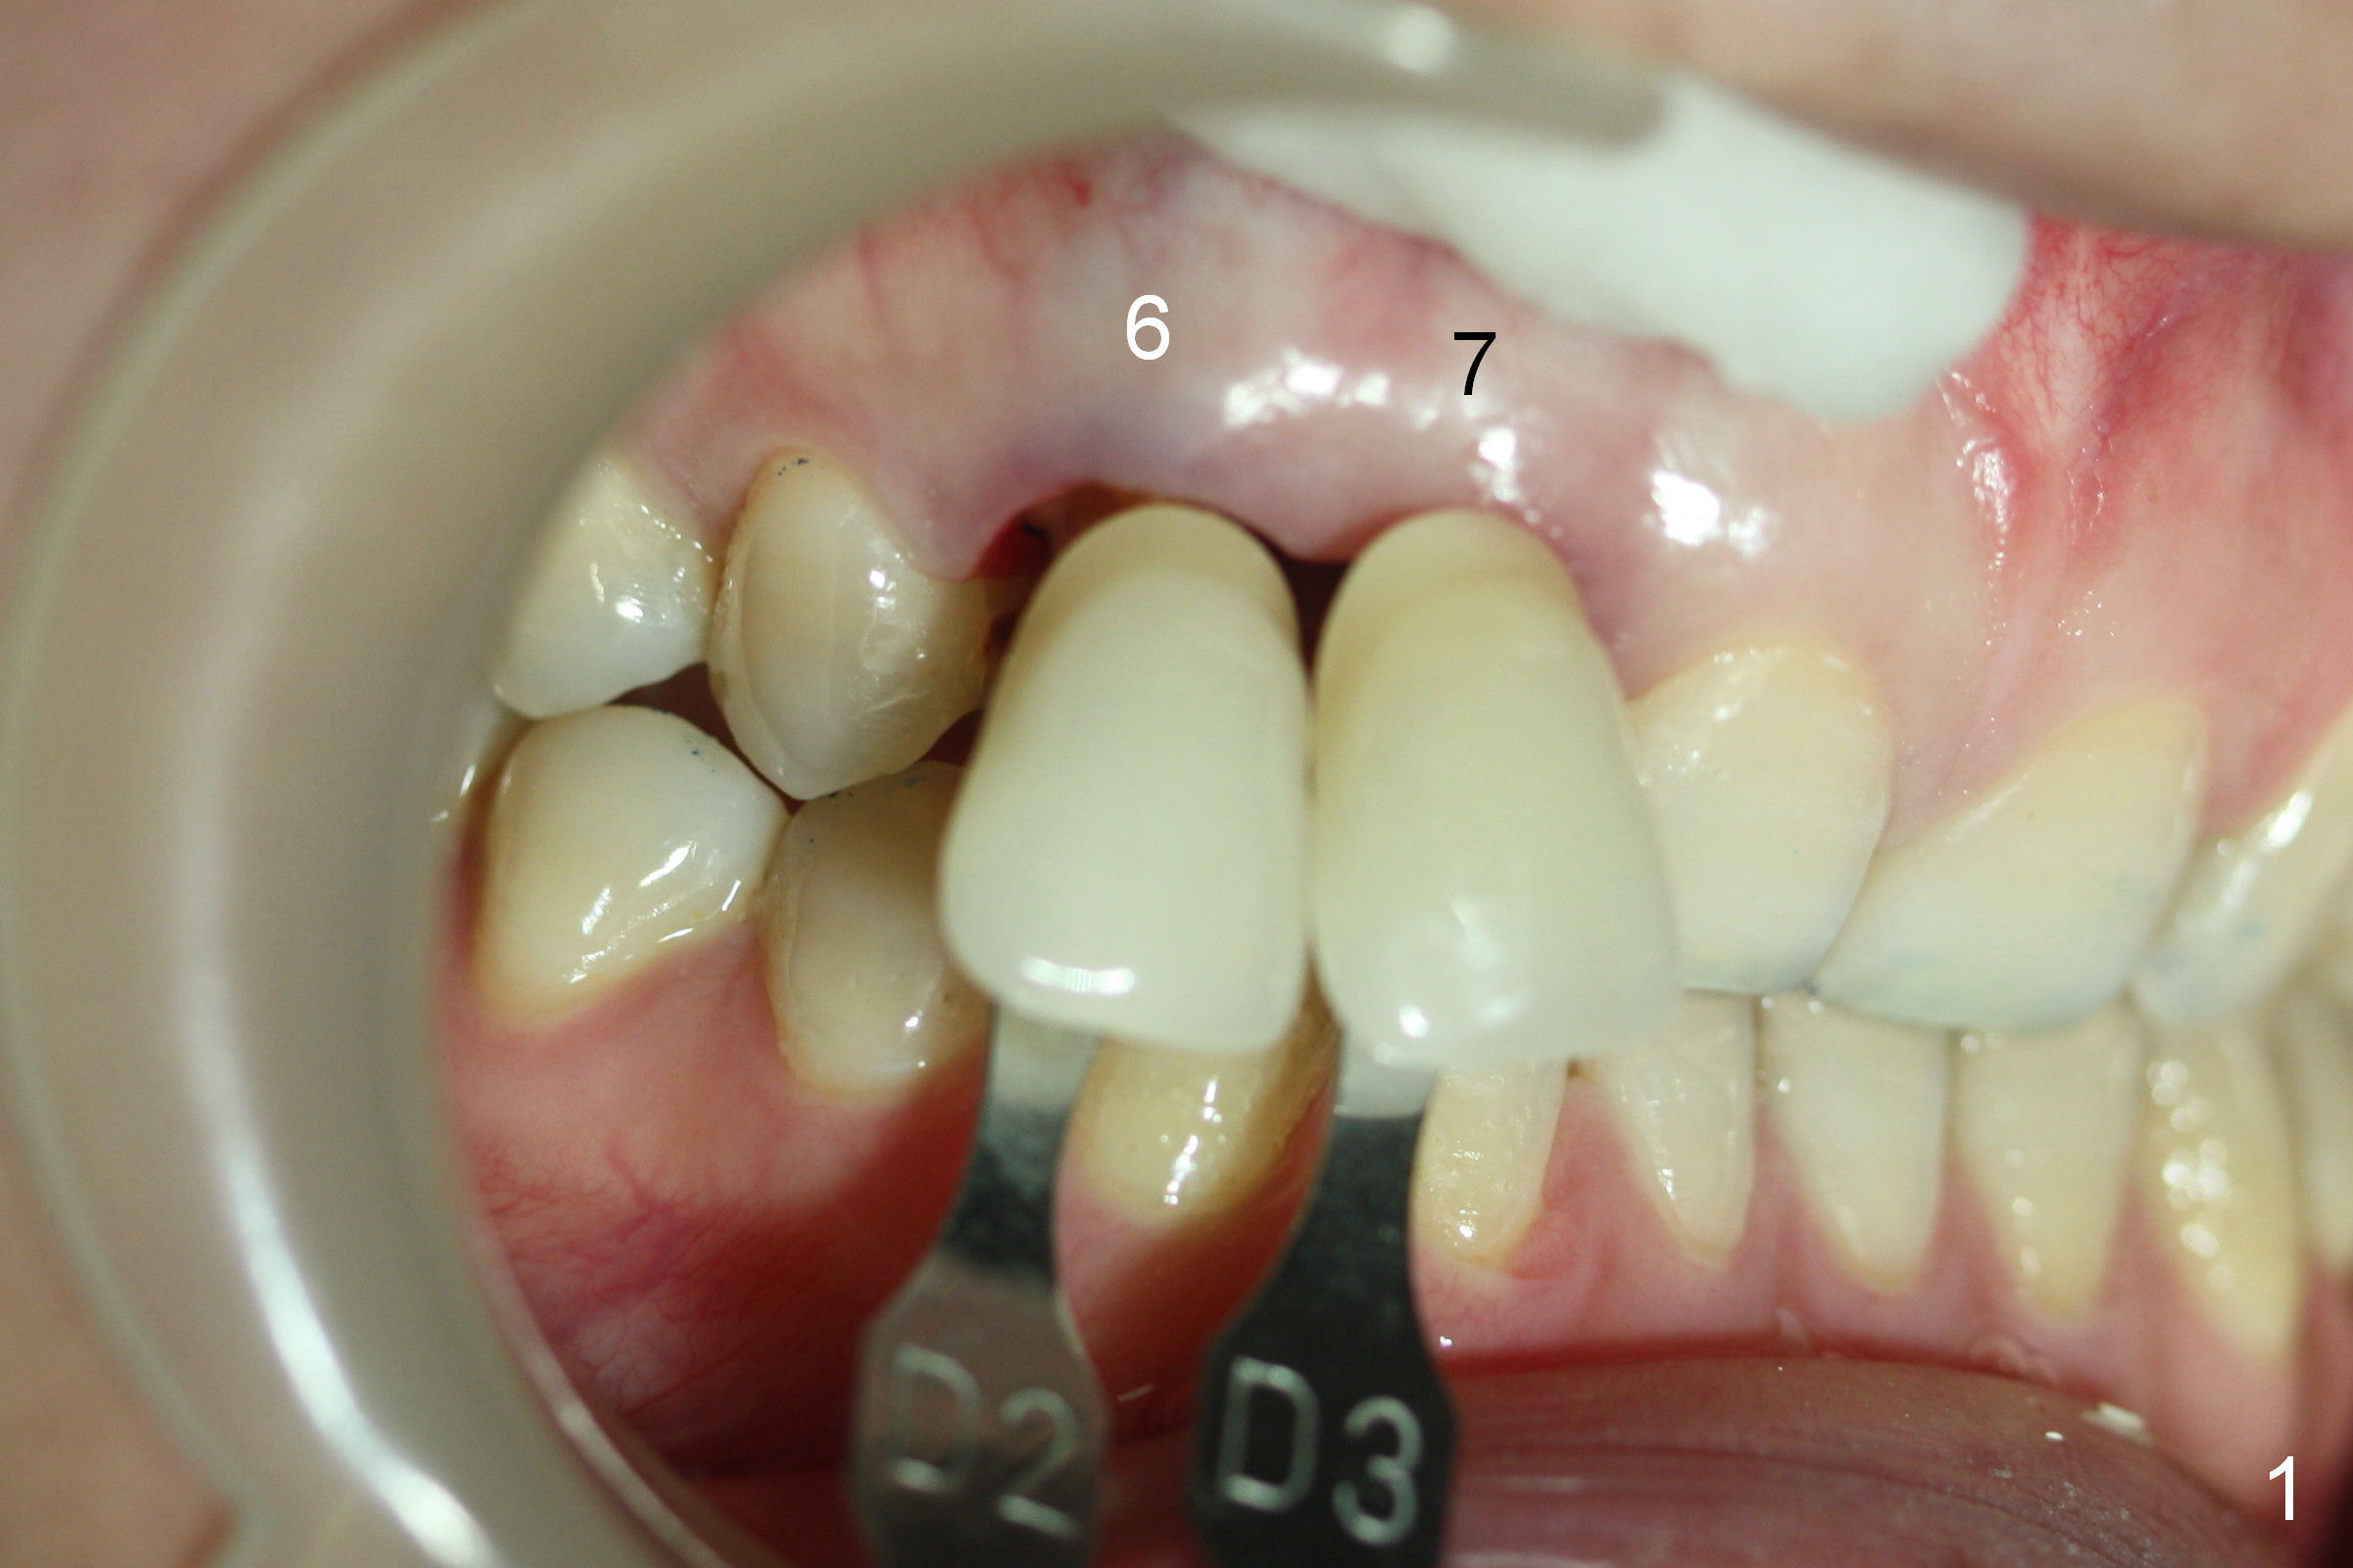

A 30-year-old lady has finished #7 RCT retreat and prefabricated post & core (Fig.1,2). Emax is chosen if it can cover the brownish discoloraton.